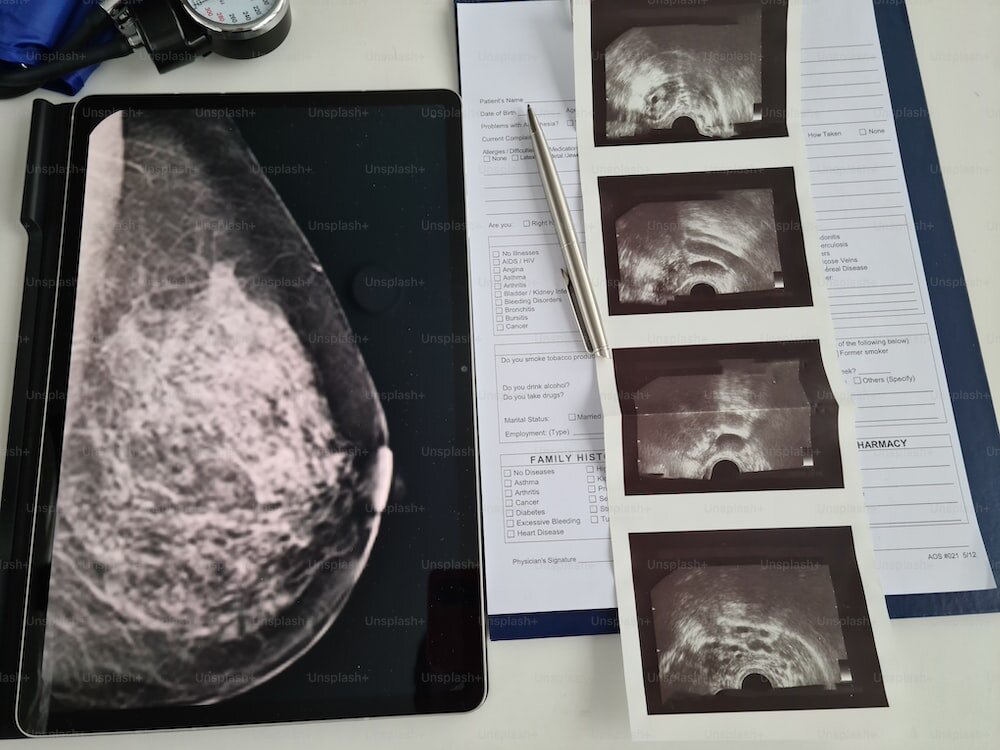

Что такое маммография?

Маммография — основной инструмент скрининга рака молочной железы. Маммографию проводят с помощью рентгеновских лучей. Снимки, полученные при исследовании, изучает и описывает врач-рентгенолог.

Это относительно недорогой метод исследования, который позволяет за короткое время посмотреть большое количество женщин. Снимки могут храниться и использоваться для сравнения в динамике. Маммография применяется для скрининга, т.е. осмотра здоровых женщин, не имеющих жалоб. Также она широко используется для диагностики заболеваний молочных желез у пациенток, имеющих проблемы.